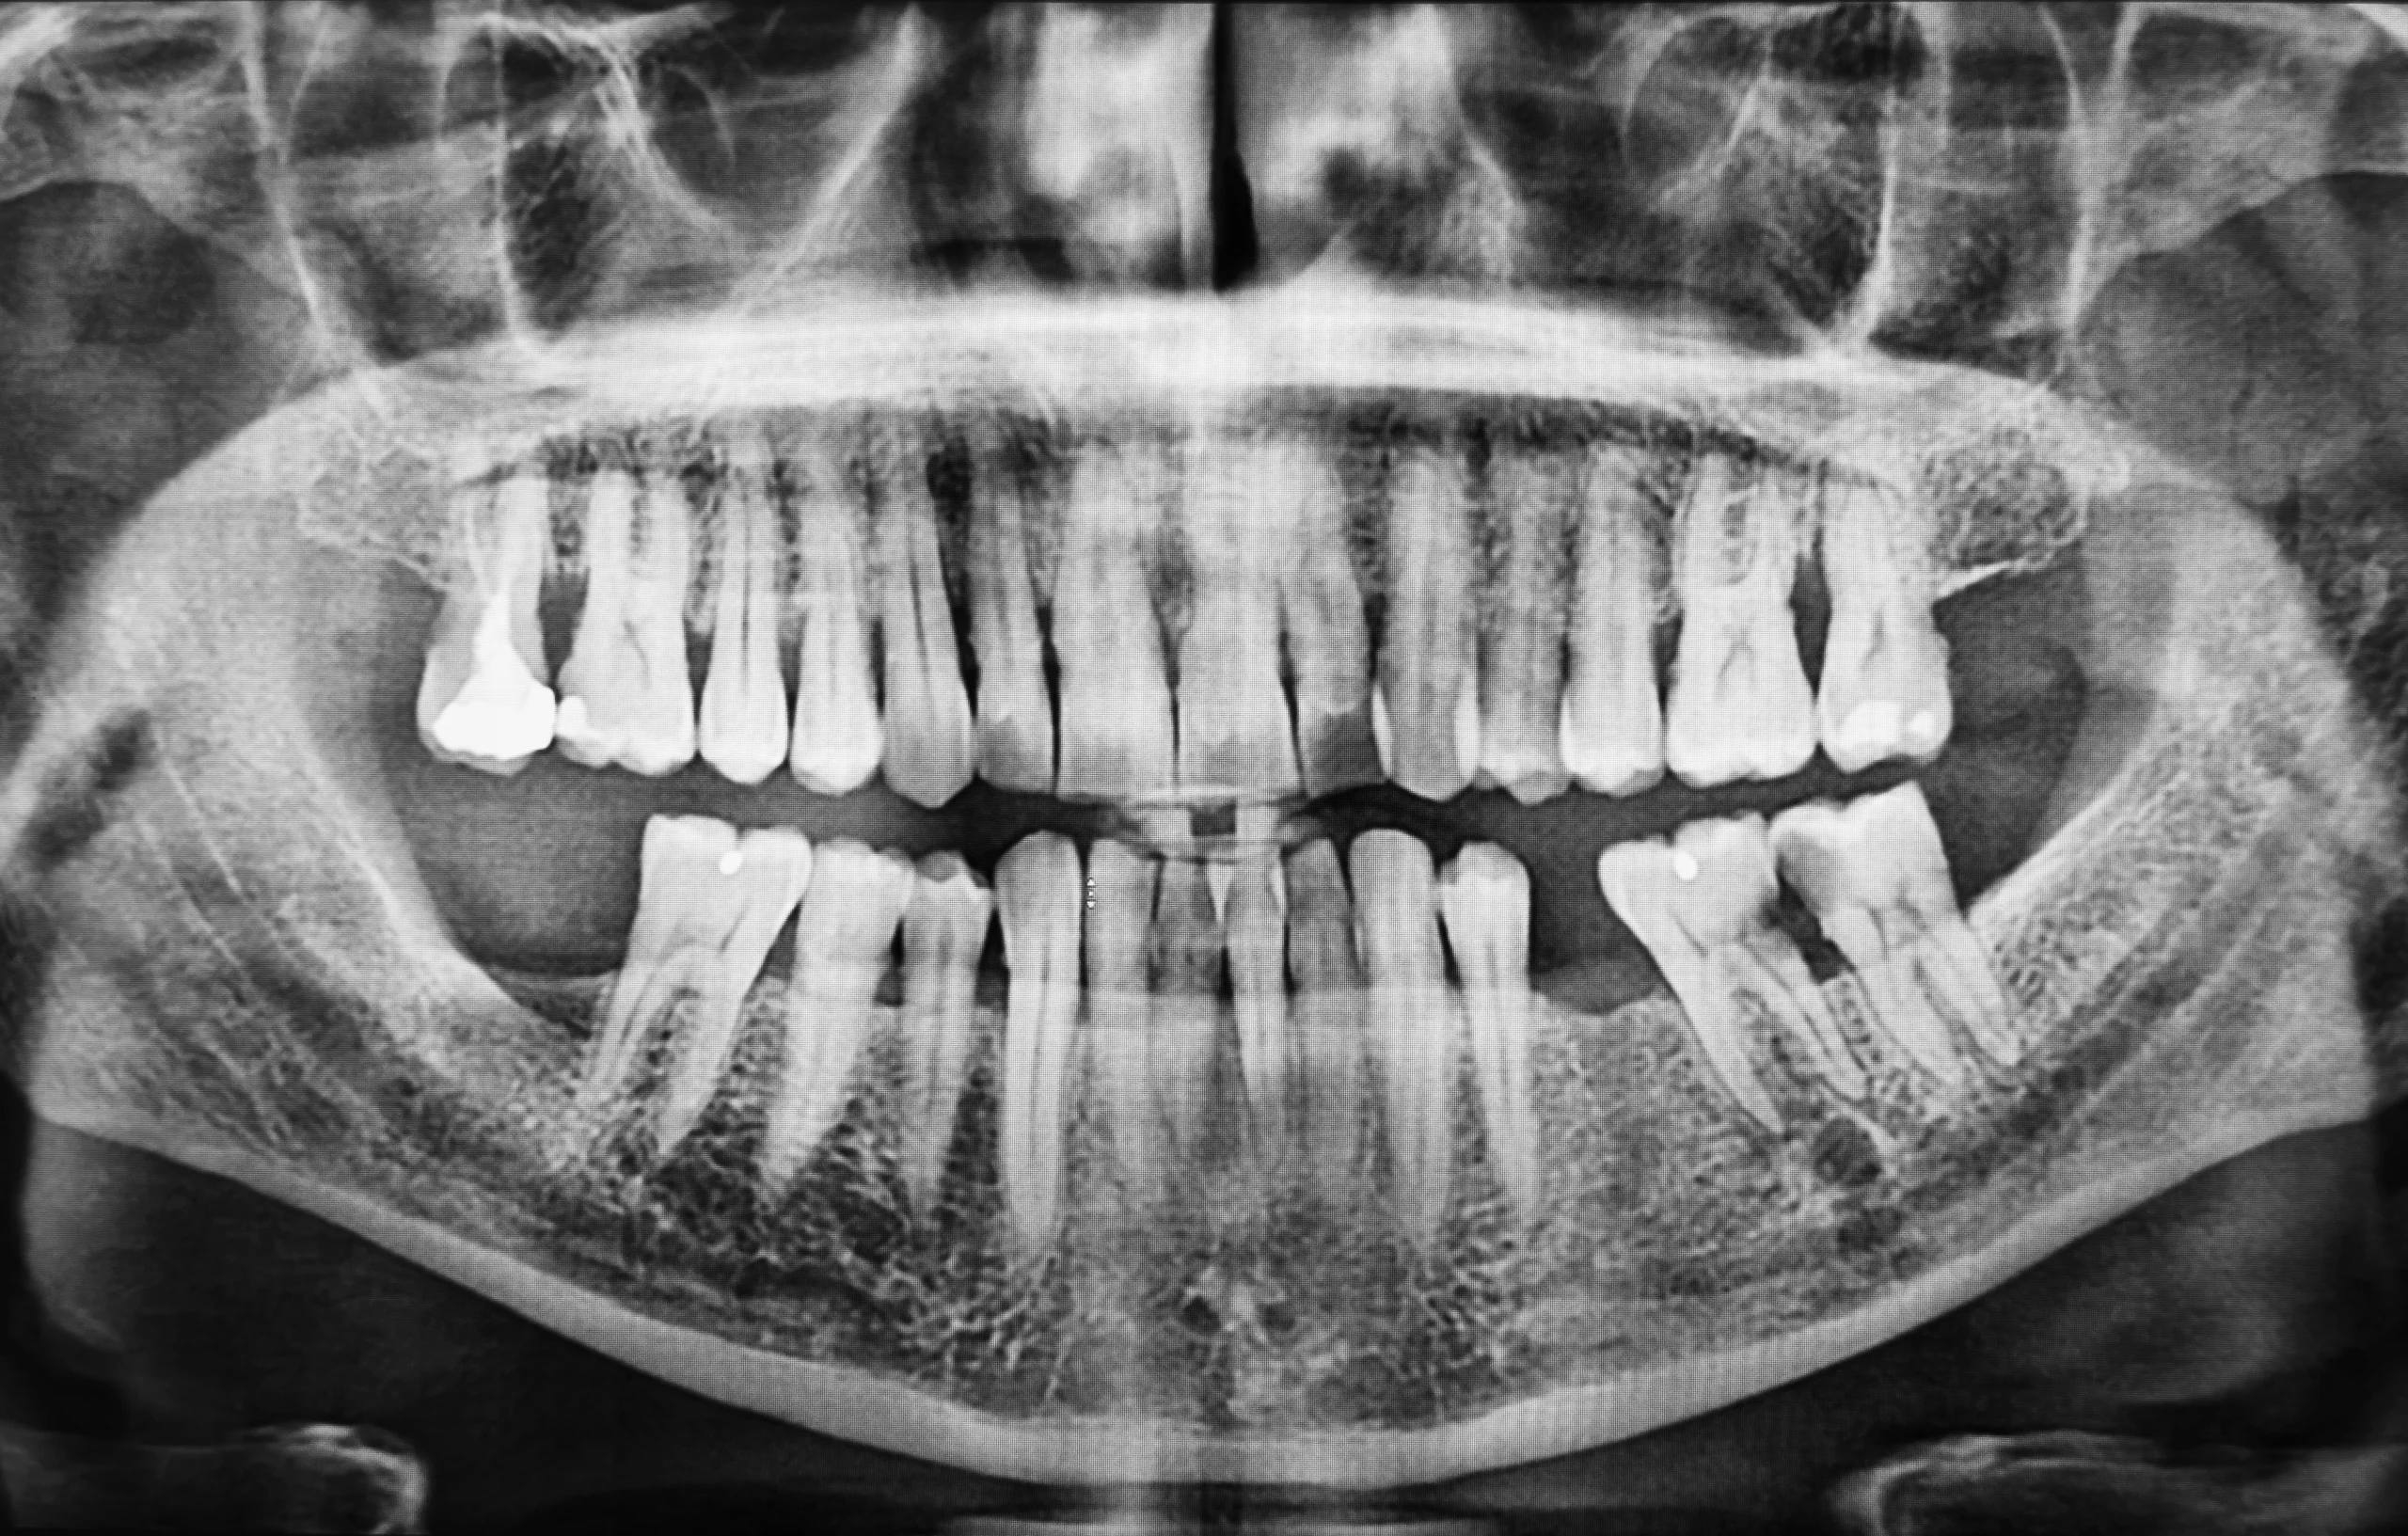

ماذا تكشف الأشعة المقطعية قبل الجراحة في زراعة الأسنان الرقمية؟

تُعد الأشعة المقطعية حجر الأساس في زراعة الاسنان الرقمية، حيث توفر رؤية ثلاثية الأبعاد دقيقة للعظم والهياكل المحيطة.

تساعد هذه الأشعة على:

- تقييم حجم وكثافة العظم

- تحديد موقع الأعصاب والجيوب الأنفية

- فهم المساحات المتاحة للغرسة

- كشف القيود التشريحية التي لا تظهر في الأشعة التقليدية

تمنح هذه المعلومات المريض فهماً حقيقياً لحالته، بدلاً من الاعتماد على تقديرات عامة، كما تساعد في توقع وقت زراعة الاسنان بدقة أكبر.

كيف يعمل التخطيط الرقمي بعد الأشعة؟

بعد تحليل الأشعة، تبدأ المرحلة الأهم في زراعة الاسنان الرقمية وهي التخطيط الافتراضي. يتم وضع الغرسة رقمياً قبل الجراحة، مع تحديد العمق، الزاوية، والمسافات بدقة متناهية.

هذا النهج المتقدم يساعد في:

- تحديد الحاجة إلى زراعة عظم

- تحسين موضع السن النهائي

- تقليل المخاطر أثناء الجراحة

- توقع مدة العلاج والتكلفة

وفي بعض الحالات، يتم استخدام دليل جراحي لنقل هذه الخطة الرقمية بدقة إلى فم المريض، مما يجعل التنفيذ أكثر أماناً وتنظيماً.

لماذا يحتاج بعض المرضى لأشعة مقطعية قبل الغرسات؟

تساعد الأشعة المقطعية الطبيب على تقييم شكل العظم، العلاقات المكانية، والهياكل التشريحية المجاورة بالأبعاد الثلاثة لضمان أمان ودقة الوضع الجراحي.